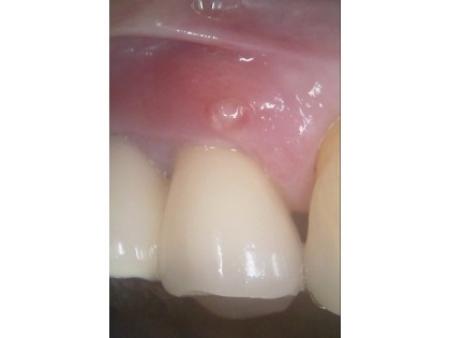

| 行ったご提案 ・治療内容 | 痛みが出ているブリッジ周辺の治療として、ブリッジの土台となっていて、歯根が割れている手前の歯(第2小臼歯)は抜き、根尖病巣を発症している奥の歯(第2大臼歯)は、根管治療を行います。 根管治療とは、感染した神経を取り除いて、歯根内部を清掃・消毒する治療方法のことです。 抜歯と根管治療を行ったあとは、欠損部を補うために、2本のインプラントを埋入する方法を提案しました。 インプラントを埋入するために必要な骨量が足りない場合は、鼻の空洞(上顎洞)の粘膜を少しずつ押し上げて骨を増やす「ソケットリフト」を併用することもお伝えしています。 インプラント治療のメリット インプラント治療のデメリット それぞれの方法について丁寧にお伝えした結果、治療に同意いただきました。 まずは、右上手前の歯(第2小臼歯)を抜きました。 抜歯後は、インプラント治療を行うために、歯を支える骨(歯槽骨)の回復を待つ必要があり、最低でも6ヶ月を要します。 約2ヶ月後、インプラントと骨が結合したことを確認して、右上奥歯2本の仮歯を作製し、手前の歯槽骨が再生するまで経過観察を継続します。 約4ヶ月後、歯槽骨の再生が確認できたため、もう1本のインプラントを埋入しました。 当院のインプラント治療は、施術の安全性と長期的な使用を可能にすることを優先して治療を行うため、通常は抜歯後に歯槽骨の治癒を待ってからインプラントの埋入を行っています。 右上奥歯2本に仮歯が入り、噛み合わせが安定した状態になったため、根尖病巣を発症している右上奥歯の治療を開始します。 また、インプラントに装着する人工歯を作製する前に、歯科医院で歯を白くするオフィスホワイトニング治療を希望されたため、治療期間がやや長くなっています。 最後に、完成した人工歯を装着し、見た目や噛み合わせに問題がないことを確認して、治療を終了しています。 |

治療後